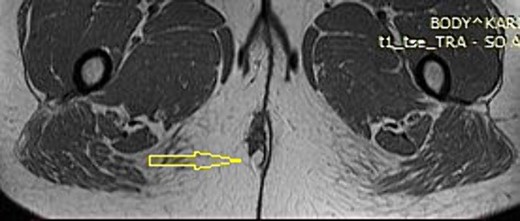

A 37-year-old female patient presented to the outpatient department with a palpable mass in the perianal region on the right side. The patient had two normal pregnancies with spontaneous deliveries 13 and 9 years ago, respectively. The medical history was remarkable for an operative treatment of perianal abscess 6 months before the examination. At the time of the surgery, the patient presented with pain and fluctuating swelling in the perianal region. An incision was performed with the evacuation of a small collection of dark fluid. After the procedure, a continuous experience with occasional pain and uncomfortable feeling in the perianal region was present. Magnetic resonance imaging (MRI) revealed a 4.5 × 2.5 cm perianal mass slightly towards the right side. It showed mixed intermediate and high signal intensity, attributed to the recurrent puss component. There was an associated diffusion restriction but no avid enhancement after intravenous contrast administration. The opacity of surrounding adipose tissue was noted. The nature of the mass was interpreted as recurrent abscess formation (Fig. 1).